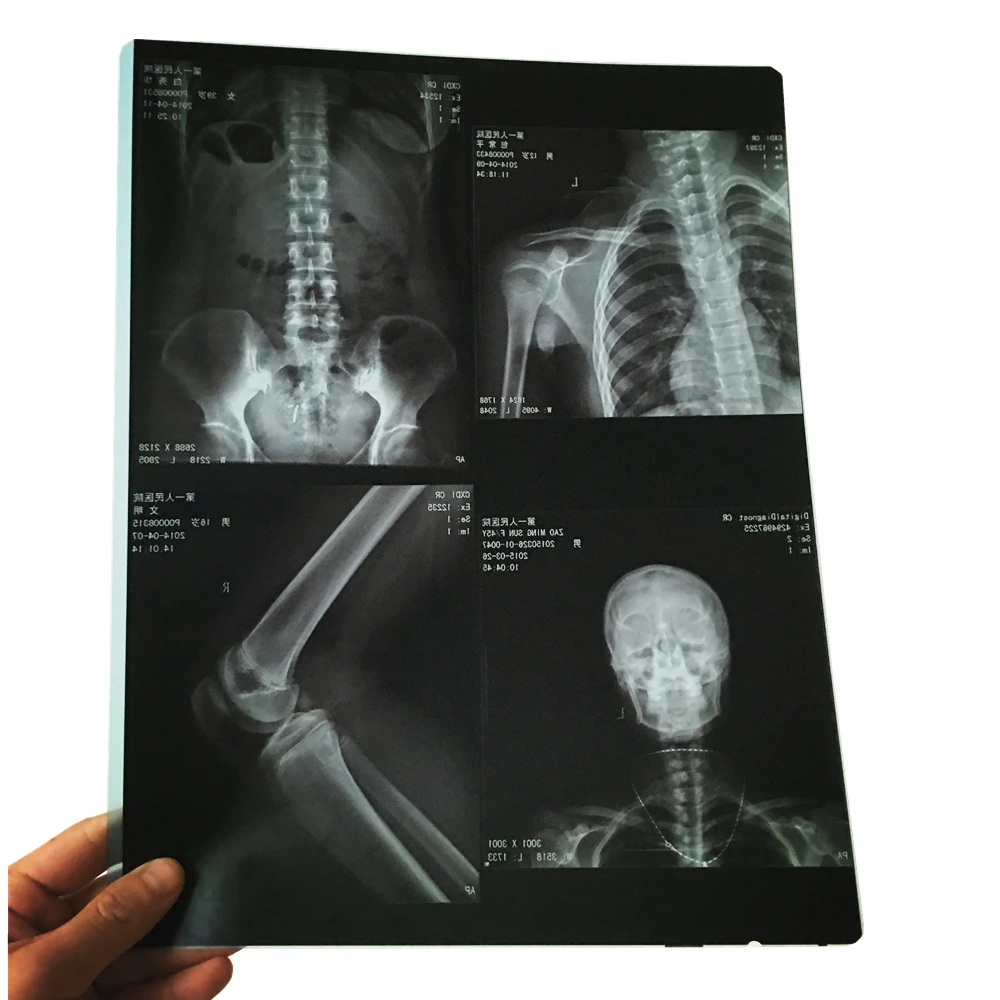

Лазерная камера для печати медицинских изображений на пленке стандарт dicom